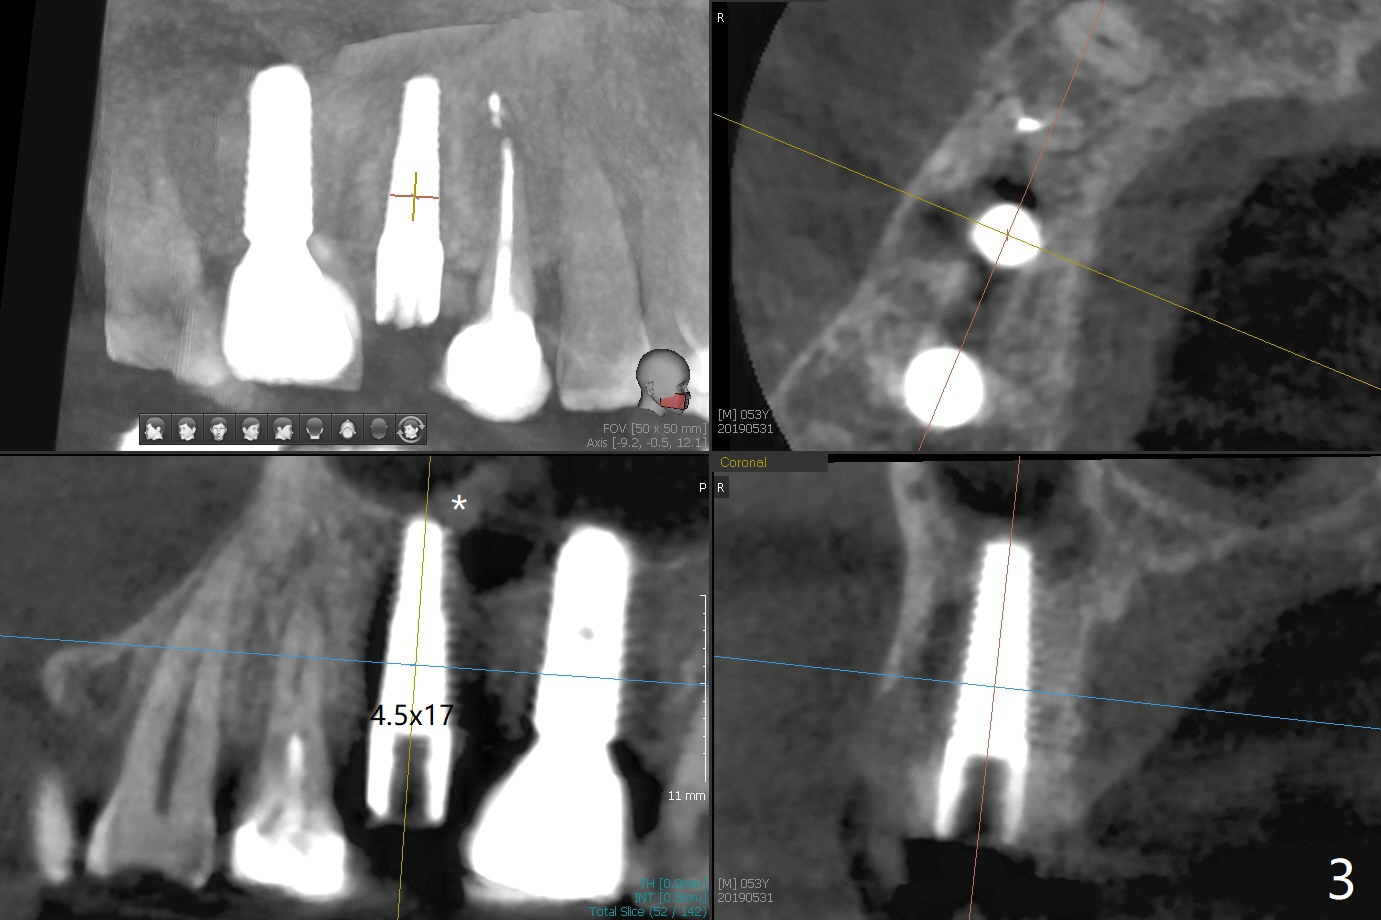

In spite of a fistula at #4, the buccal plate is present because of the exostosis (Fig.1 *). Since the socket is long and narrow, it is difficult to initiate osteotomy in the distal slope. Since the buccal plate is low, osteotomy is established as palatal as possible. The sinus floor is thin, but hard to elevate with Magic Sinus Lifter. Use of 3 mm Magic Expander leads to sinus floor break through and membrane perforation. After increase in the osteotomy with sequential expanders, a 5x20 mm tap is inserted with stability (Fig.2). Two pieces of PRF membrane are inserted for sinus membrane repair, followed by small amount of allograft (mixed with PRF, Fig.3 *) and a 4.5x17 mm dummy implant. A 5x17 mm tissue level implant is placed with >45 Ncm; with immediate placement of a 4x3 mm abutment (Fig.4), an immediate provisional is fabricated. There is no postop nasal hemorrhage. The immediate provisional has occlusal perforation 1.5 months postop. The tooth #13 has mobility due to its overuse and missing the teeth #14 and 18. Bitewing taken while redoing crown for #30 shows that the implant threads are subcrestal (Fig.5). There is no crestal bone resorption 6.5 months postop (Fig.6,7), while the periradicular radiolucency decreases (Fig.7).